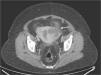

Ante los hallazgos clínicos y analíticos, se decide realizar un estudio de tomografía computarizada (TC) abdominopélvica, que mostró un colección mal delimitada, hipodensa, entre la pared lateral izquierda del útero y el ovario adyacente, con infiltración de los planos grasos adyacentes. Se observa una segunda lesión de las mismas características parauterina derecha y ligera hidronefrosis ipsolateral (fig. 1). Posteriormente, a fin de descartar progresión de la enfermedad oncológica, se realizó un estudio de resonancia magnética (RM) pélvica que mostró la presencia de colecciones a ambos lados del útero, hipointensas en secuencias T1 e hiperintensas en secuencias T2, con una marcada restricción en secuencia de difusión, hallazgo indicativo de corresponder a contenido purulento. En las imágenes potenciadas en T2 se muestra una discontinuidad en la pared uterina izquierda, permitiendo la comunicación de la colección con el interior del útero (figs. 2 y 3).